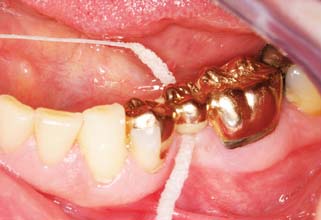

Patients with cast restorations should attend recall visits at least every 6 months. Less frequent recall may lead to oversight of recurrent caries or the development of periodontal disease. Patients who have been provided with extensive fixed prostheses (Fig. 32-6) need more frequent recall appointments, particularly when advanced periodontal disease was present. The appointments can be coordinated by the restorative dentist or the periodontist. To ensure treatment continuity, it is imperative to establish in advance who will assume primary responsibility for coordinating recall appointments.

Fig. 32-6 Patients who have received extensive treatment of this nature require more frequent follow-up care.

Unfortunately, periodontal disease often occurs after placement of fixed prostheses,26 especially where the cavosurface margin has been placed subgingivally27-29 or the prosthesis is overcontoured.30 Inflammation is more severe with poorly fitting restorations31 (Fig. 32-12), but even “perfect” margins have been associated with periodontitis.32 At recall appointments, particular attention is given to sulcular hemorrhage, furcation involvement, and calculus formation as early signs of periodontal disease. Improperly contoured restorations should be recontoured or replaced.

Fig. 32-12 Periodontal failure resulting from defective fixed prostheses. A, Inadequate margins and contour. B, Appearance before surgery. C, Flap reflected. D, Appearance after surgical recontouring. E, Radiograph of new cast restorations. F, Replacement restorations.